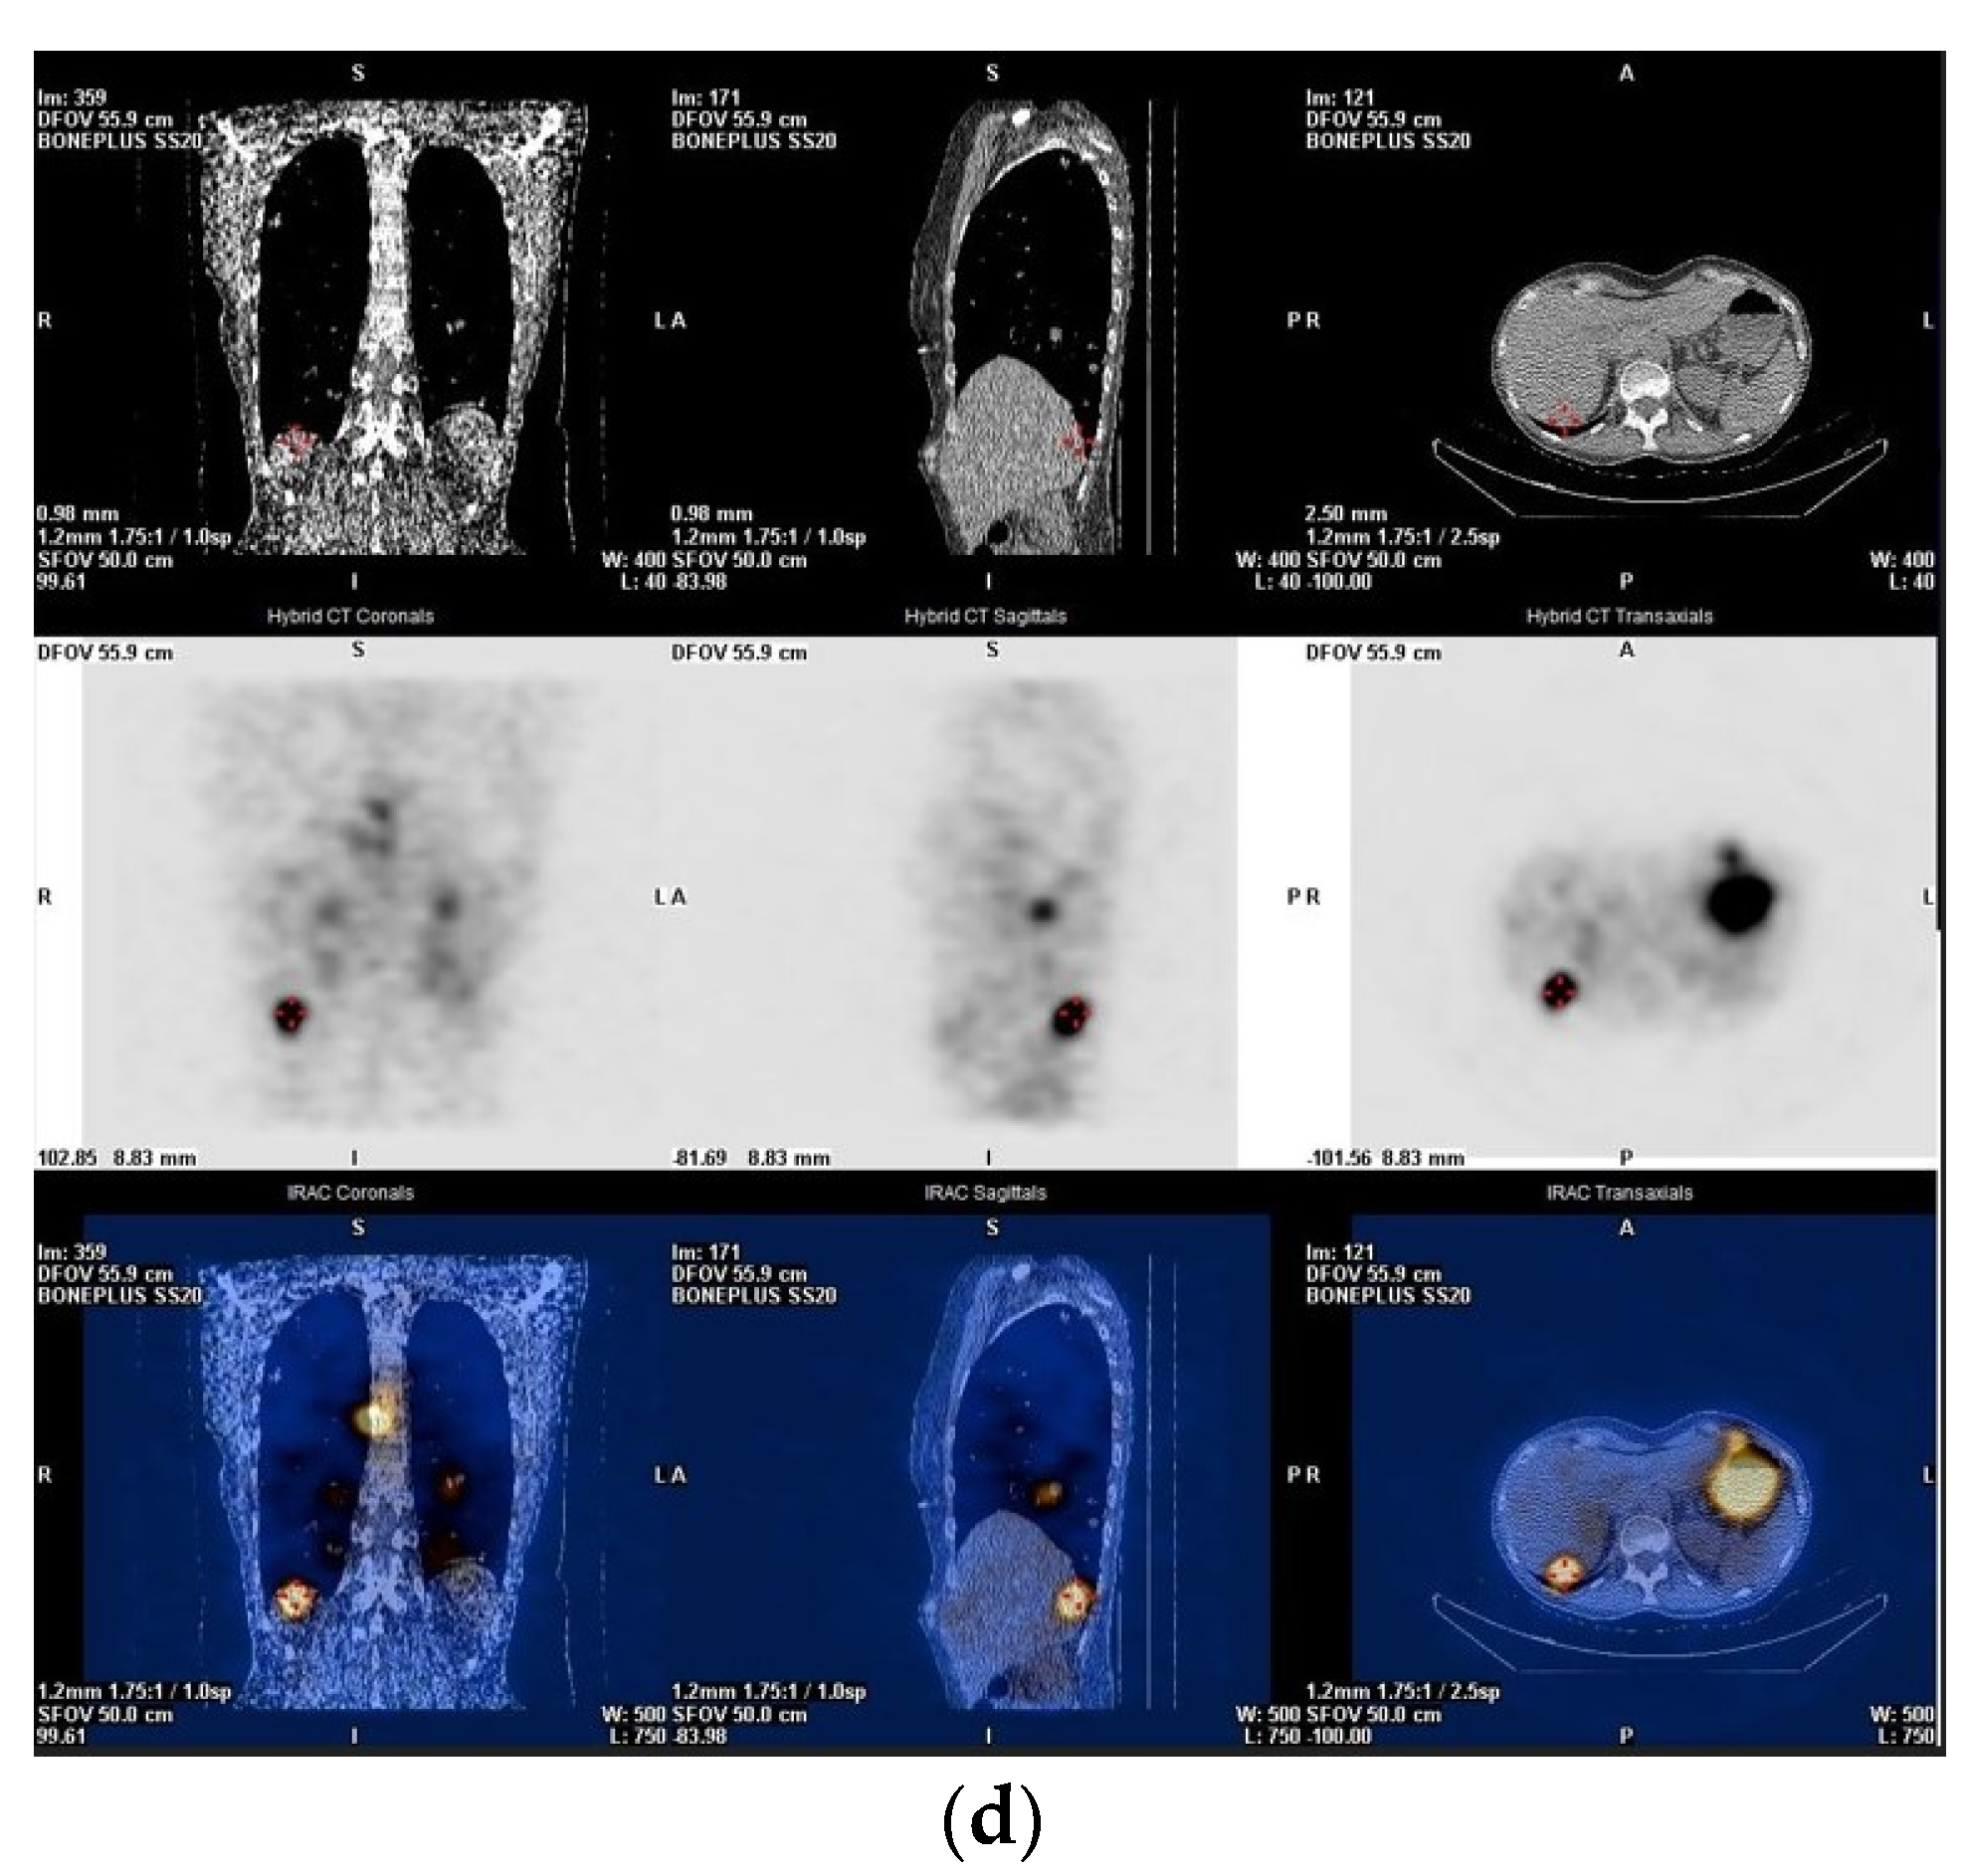

2. Pre-Treatment Whole-Body Imaging

3. Post-Treatment Whole-Body Imaging